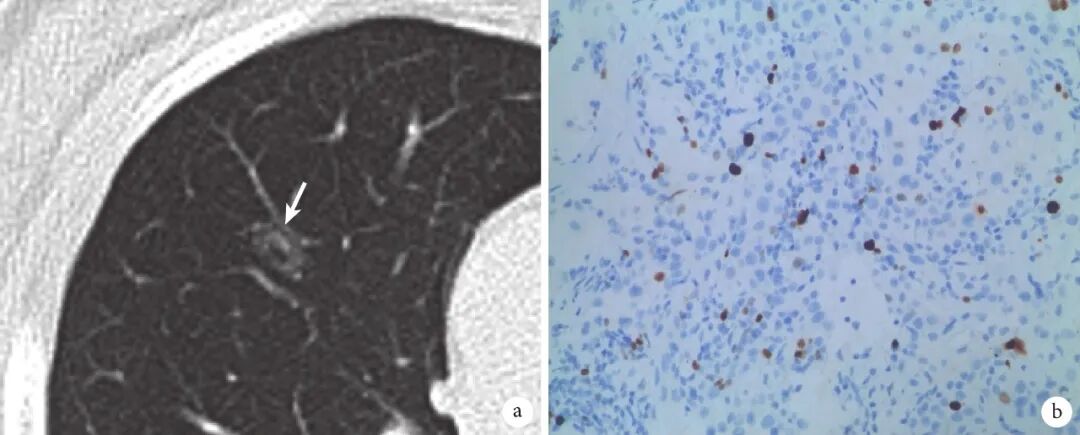

图4 混合磨玻璃结节肺癌患者影像学表现及病理

a:结节(箭头)长1.3 cm×0.8 cm,有分叶、毛刺、胸膜凹陷和血管集束征,CTR<50%,组织病理学证实为IAC,ⅠA2期;b:Ki-67表达10%(×200);CTR:实性成分比例;IAC:浸润性腺癌